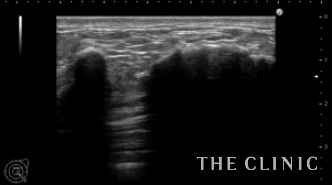

エコー所見です。

触診では左右に1個づつの7㎝大のしこりを触れましたが、エコーではさらに左に2つの石灰化したしこりを認めました。